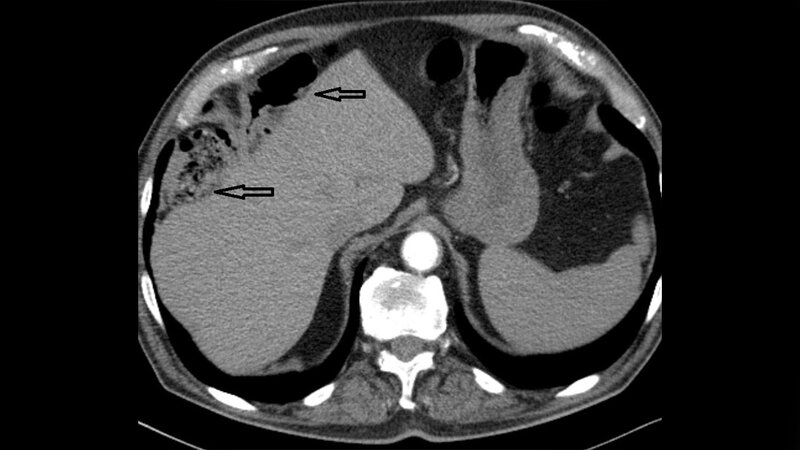

Das Chilaiditi-Zeichen, die Darminterposition zwischen Diaphragma und Leber, ist eine gutartige Veränderung mit ausgesprochen seltener chirurgischer Konsequenz. Die Bedeutung liegt eher in der Differenzialdiagnostik und dem zeitlichen Management ernster Komplikationen. Das Chilaiditi-Syndrom kann intermittierend und episodisch auftreten.

Chilaiditi’s sign, the bowel interposition between diaphragm and liver, is a benign condition which rarely requires surgery. Its clinical importance lies in adequate differential diagnostic approach and timely management of potentially serious complications. Chilaiditi syndrome may be intermittent and episodic.